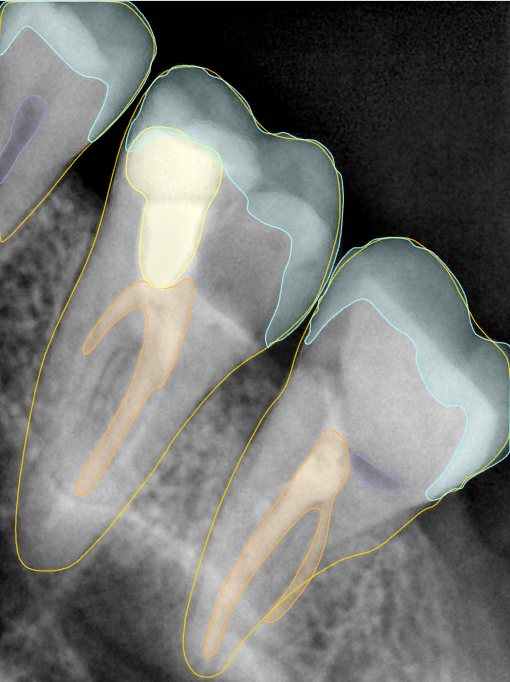

CR/DR 牙齿分割阶段记录

当前进展

- 完成了 CR/DR 牙齿相关分割训练

- 当前结果已经达到阶段预期,但仍有细节问题需要继续处理

相关测试

遇到的问题

- 训练过程中出现过 mask 下移问题

- 部分结果会出现 box 填充异常

- mask 边缘仍然有比较明显的锯齿感